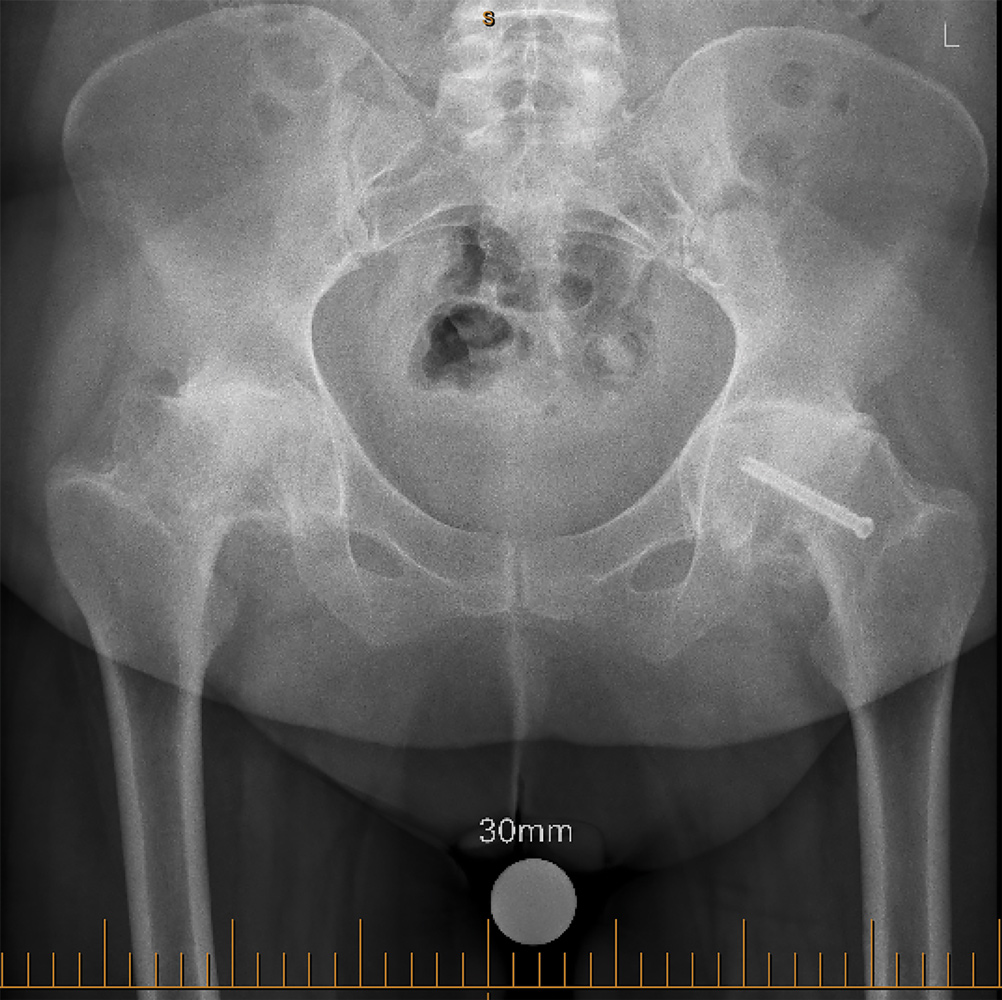

In the rapidly evolving landscape of orthopaedic surgery, the integration of robotic assistance in hip and knee arthroplasty, in my opinion, has become a game-changer.